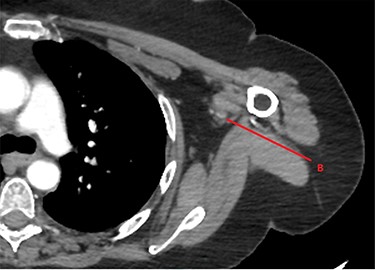

Approximately an hour later, she developed symptoms of pain and weakness to her left arm (the opposite side). Her arm was clinically assessed as cool to touch with a delayed capillary refill with pulses absent. A computed tomography angiogram (CTA) of her left arm was arranged which revealed an abrupt stop in the left axillary artery (Figs 2 and 3) with reconstitution of the vessels in the antecubital fossa. She was taken to theatre for a brachial embolectomy to re-establish blood flow to her acutely ischaemic arm.

CTA of left upper limb in the transverse plane. B—axillary artery without contrast showing occlusion due to embolism as evident in transverse imaging at B-line (see Fig. 2).